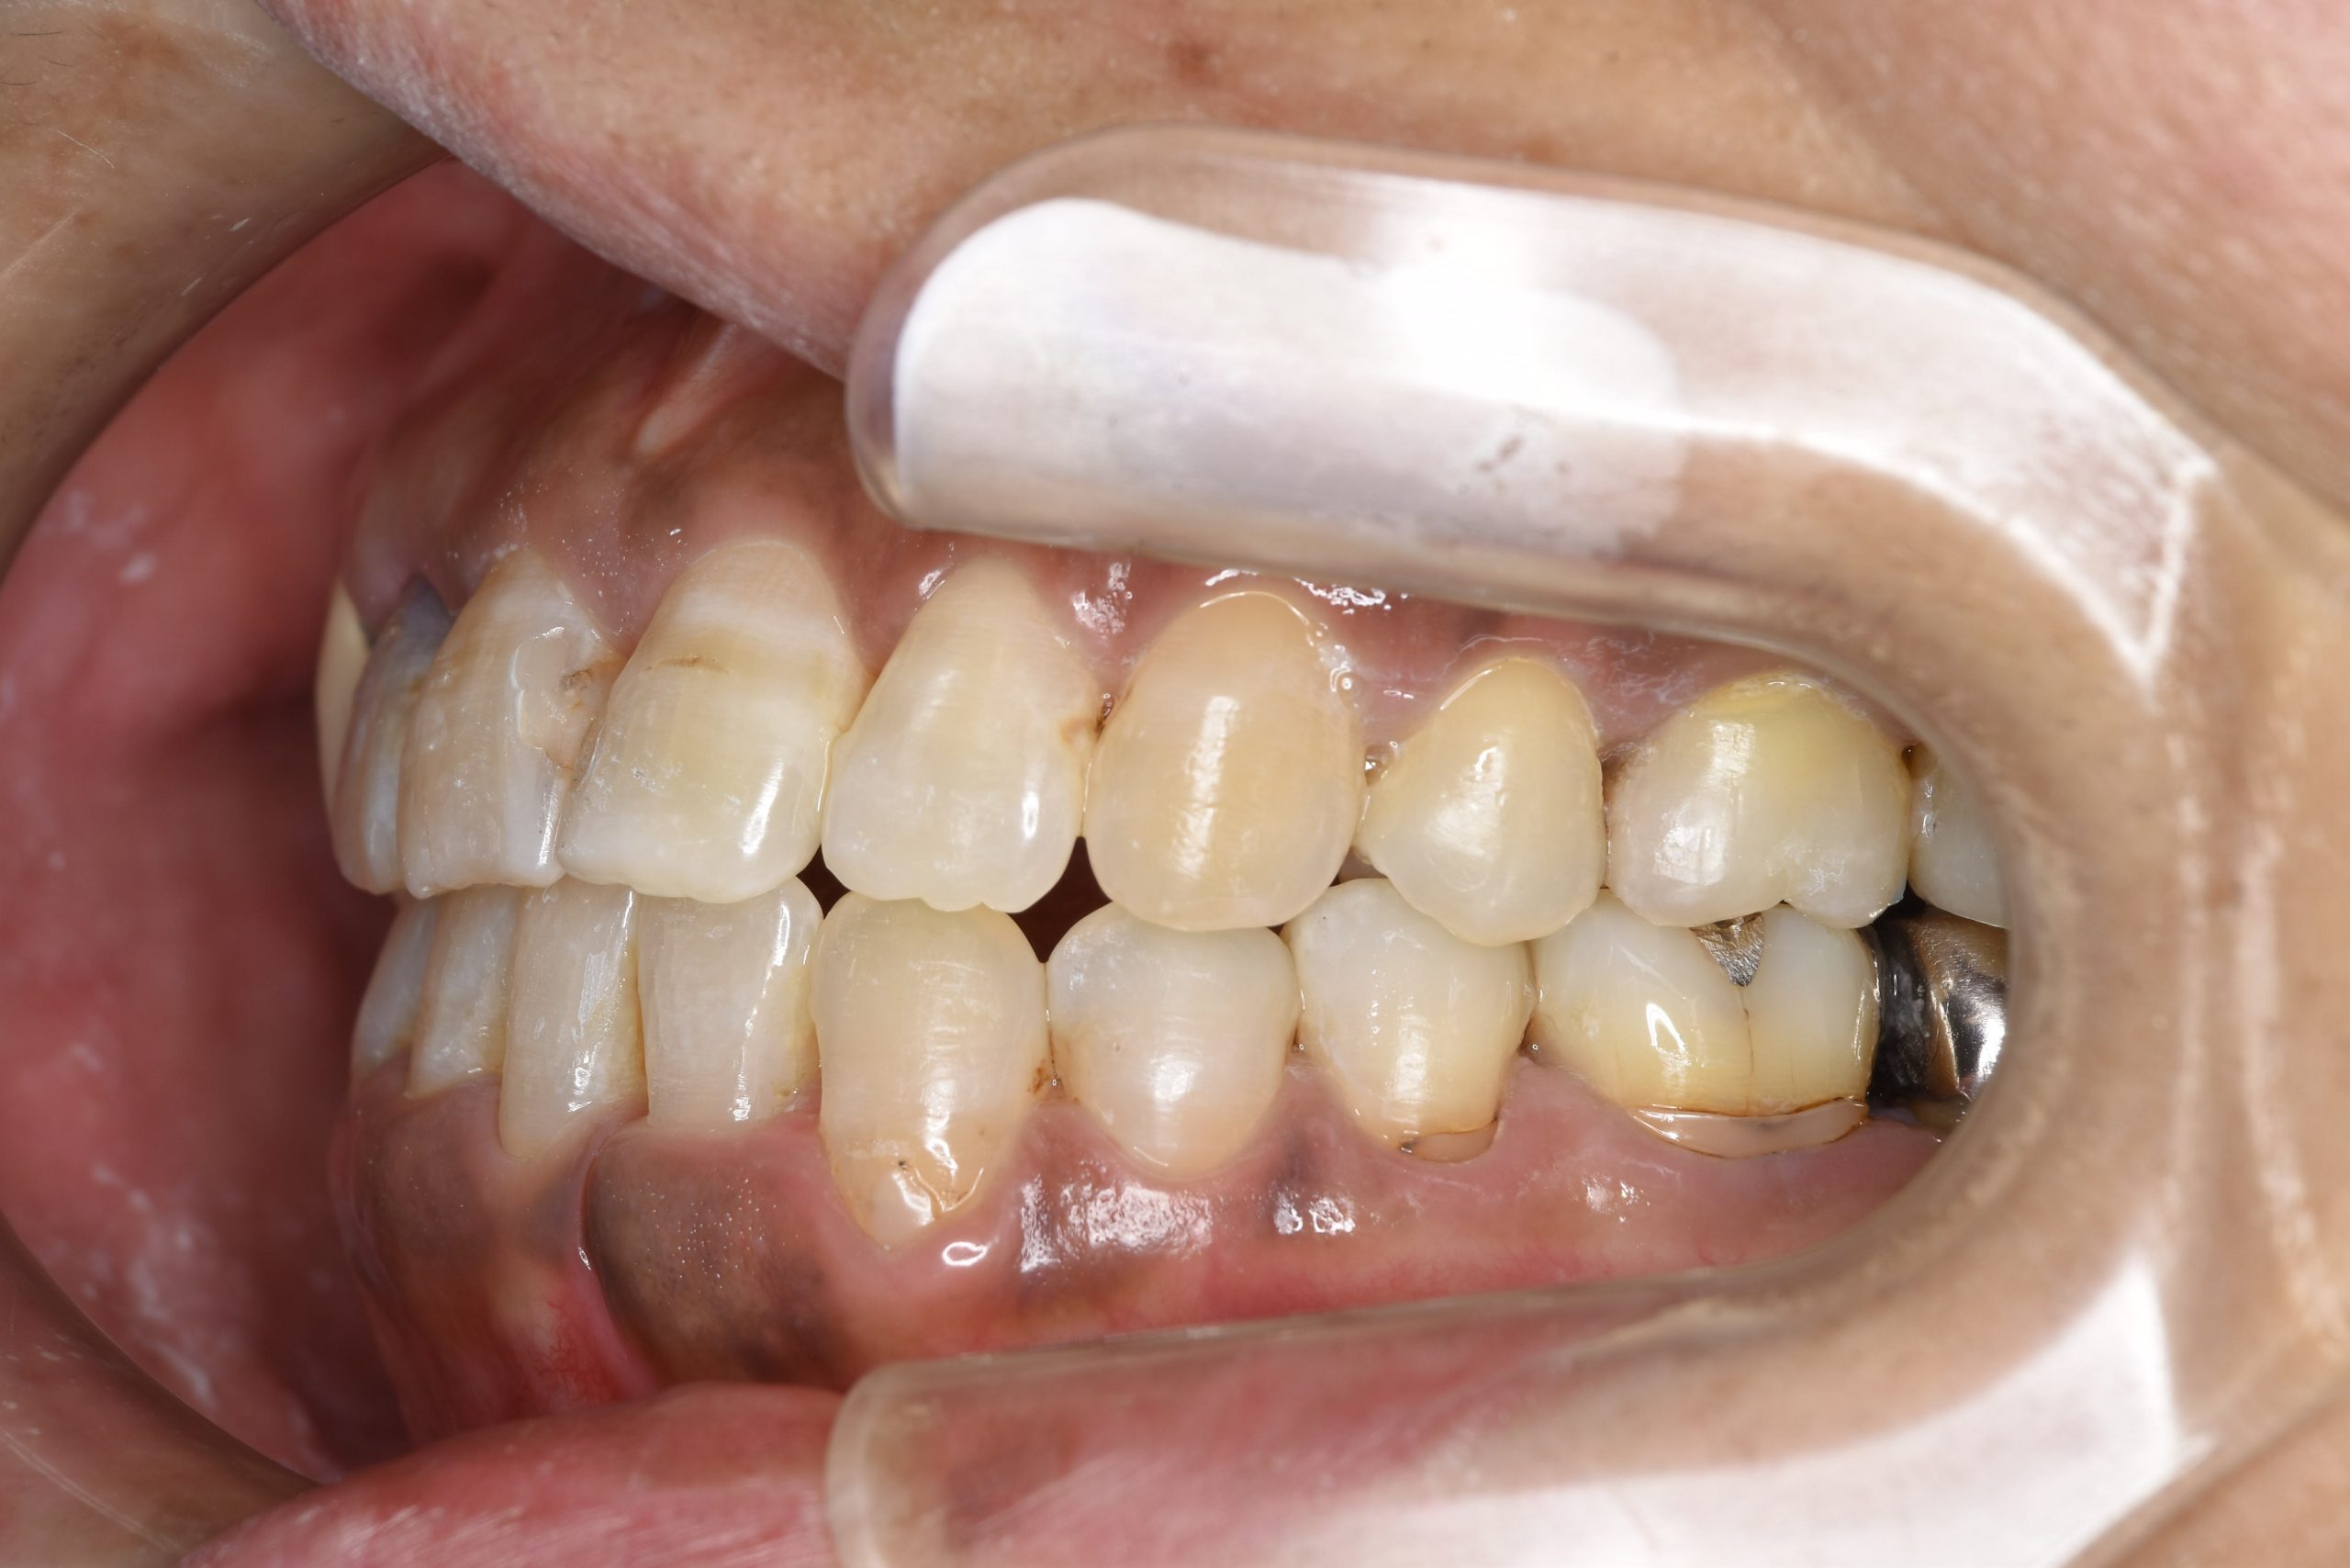

ビフォー

ワイヤー矯正治療|症例_588

主訴 かみ合わせ ※抜歯あり

施術内容 MSEと下顎リンガルアーチを用いて上下顎骨を拡大した。

その後下顎前歯を1本抜歯してマルチブラケット装置を用いて

歯牙を配列し良好な咬合を獲得した。側貌は改善した。